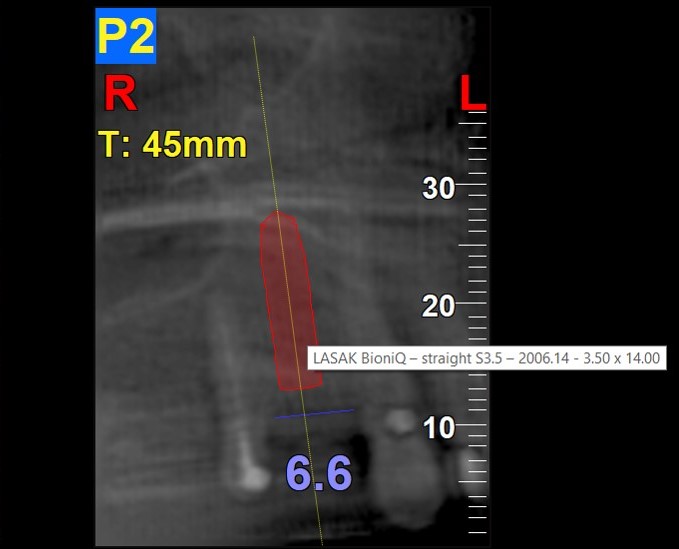

A CBCT scan of the maxilla was taken and then merged with the model scan using the coDiagnostiX software. A fixed metal-ceramic dental bridge on teeth 17-15 and a metal-ceramic implant-supported bonded dental crown for region 14 were planned and designed.

Based on the measurement of the bone volume, a 14 mm long BioniQ Straight implant with a diameter of 3.5 mm was planned for region 14.

In order to make the implant placement as precise as possible (given the limited bone supply and the implant length of 14 mm) and to avoid the nearby root of the neighboring tooth, a combined surgical template was designed.